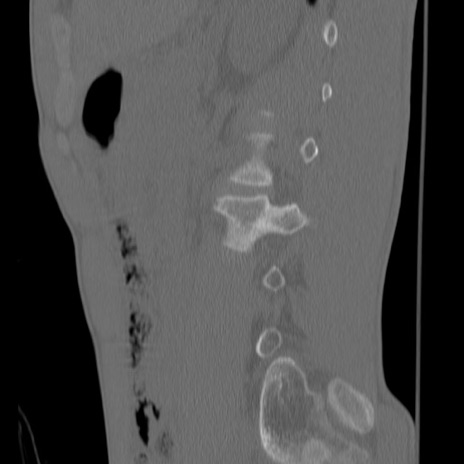

症例3 腰椎CT(矢状断像)

【症例】30歳代男性

【主訴】腰痛

【現病歴】本日旅行先で観光中に、友人と衝突し転倒し受傷。

【身体所見】麻痺なし、右下腿内側前面外側、左下腿内側に知覚鈍麻・しびれ

異常所見と診断は?

腰椎CT